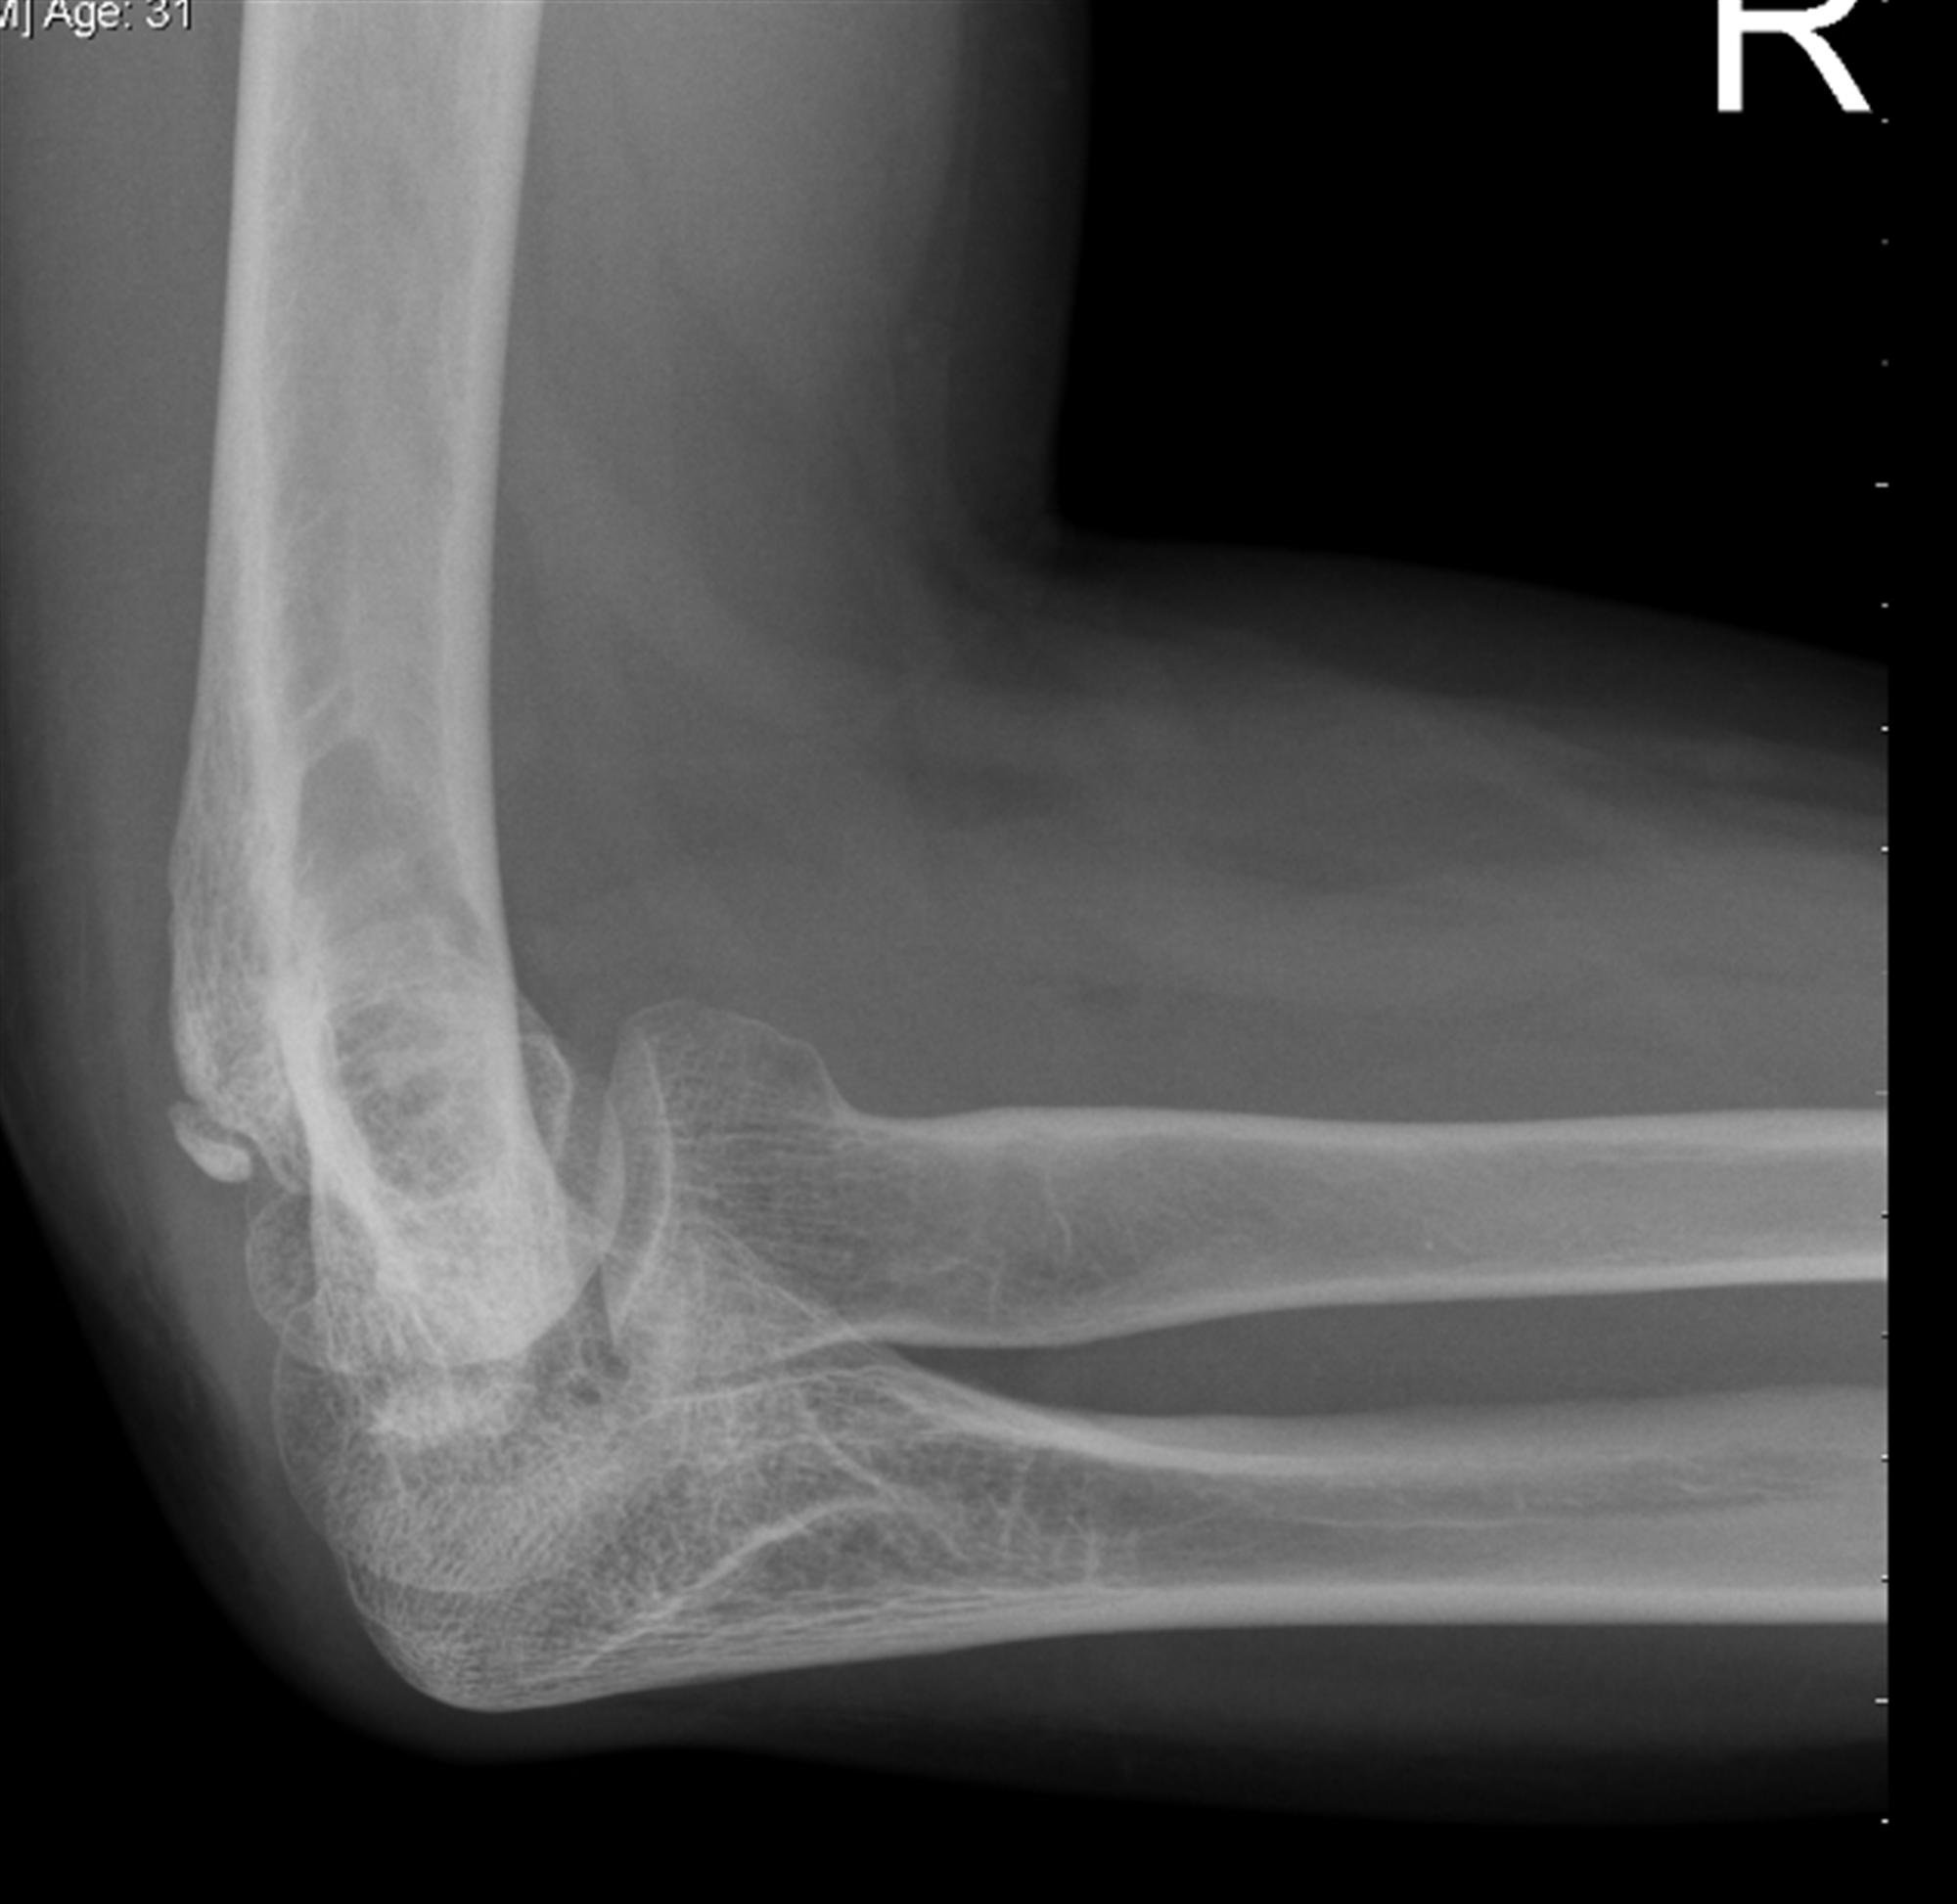

FIGURE A AAyearold male patient with cubital tunnel syndrome caused Cubital Tunnel X Ray A review article on the diagnosis and treatment of cubital tunnel syndrome, a common peripheral nerve compression disorder of the. The cubital tunnel is bordered medially by the humeral and ulnar heads of the fcu, and anteriorly by the medial epicondyle. Learn about the ulnar nerve compression and entrapment at the elbow joint, also known as cubital tunnel syndrome. The. Cubital Tunnel X Ray.

FIGURE E A AAyearold male patient with cubital tunnel syndrome caused Cubital Tunnel X Ray Learn about the ulnar nerve compression and entrapment at the elbow joint, also known as cubital tunnel syndrome. Learn about the imaging features of cubital tunnel syndrome, a peripheral neuropathy caused by compression or irritation of ulnar nerve at elbow. A review article on the diagnosis and treatment of cubital tunnel syndrome, a common peripheral nerve compression disorder of the.. Cubital Tunnel X Ray.